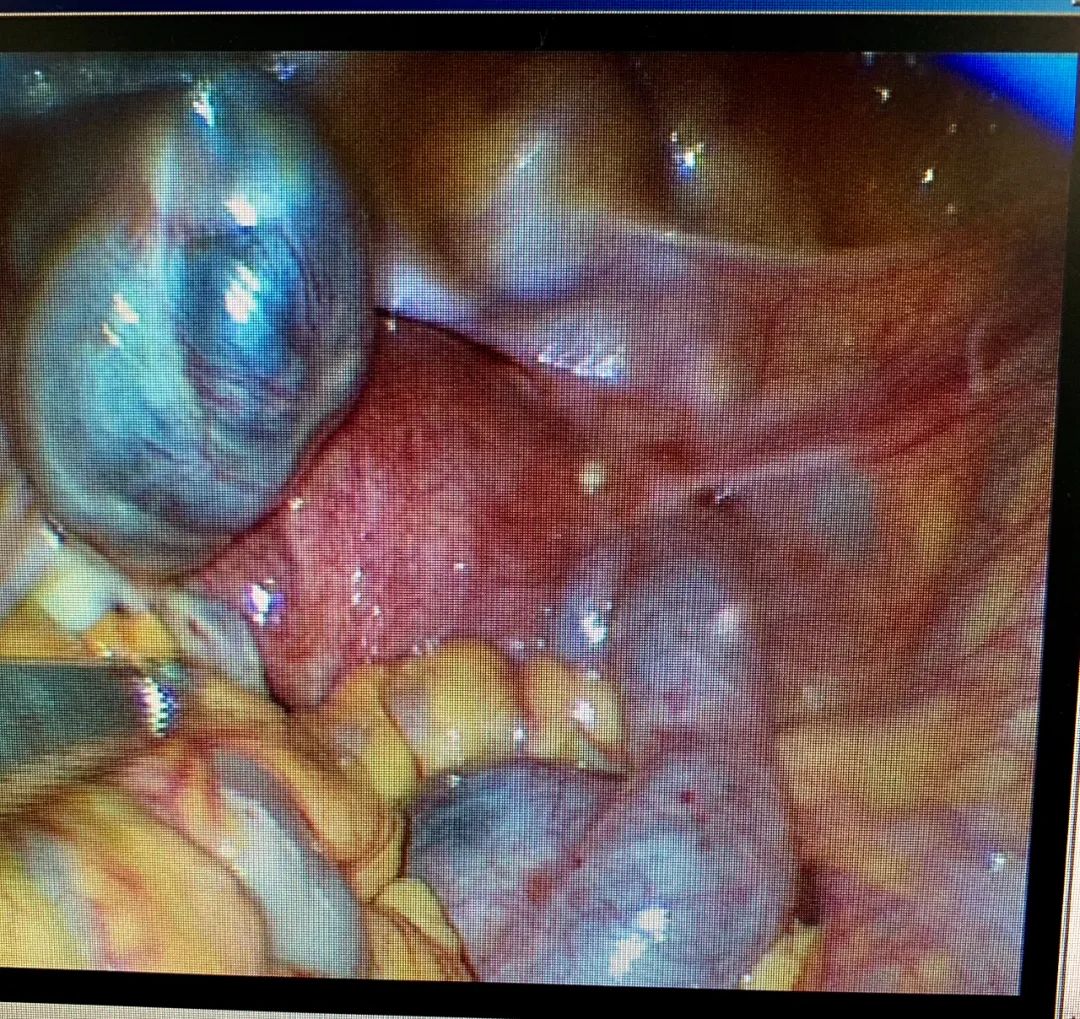

经讲解,蕾蕾接受了微创手术建议。昨天下午我们为其实施单孔腹腔镜手术,术中见双侧输卵管重度扩张、积水明显,呈现腊肠样、袋状,末端盲端、不见伞粘膜。如此严重的输卵管病变,不处理,永无怀孕可能。

LAP:双侧输卵管重度扩张、积水